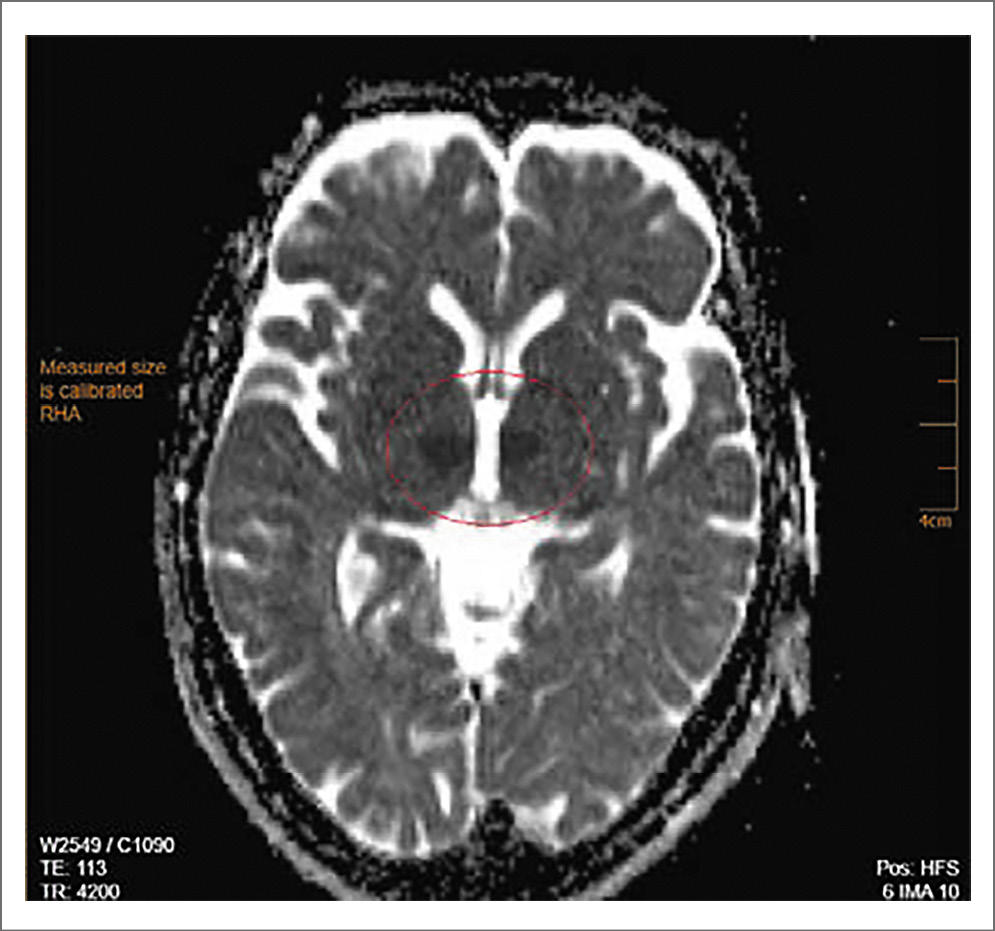

Состояние больной через 1 ч после поступления в стационар ухудшилось, в течение нескольких минут наросла общемозговая симптоматика до комы. На экстренной магнитно-резонансной томографии (МРТ) ГМ, выполненной по программе head general SE, TSE, TOF, TIRM c толщиной срезов 1, 4, 5 мм в аксиальной, сагиттальной и фронтальной проекциях с 3D-реконструкцией виллизиева круга без внутривенного контрастного усиления, обнаружены очаги острейшей ишемии в области таламусов с обеих сторон в бассейне таламоперфорирующих артерий размерами 1,0×1,2 см справа и 1,1×0,9 см слева. На времяпролетной МР-ангиографии виллизиева круга МР-сигнал от обеих задних мозговых артерий в сегменте P1 ослаблен. Признаки сосудистой мальформации и аневризмы сосудов ГМ не определены. Заключение МРТ-исследования: очаги острейшей ишемии в области таламусов с обеих сторон, стеноз обеих задних мозговых артерий в сегменте P1 (возможно, гипоплазия); рис. 1–3.

Рис. 1. Пациентка С., 72 года. МРТ-исследование ГМ 20.02.2020: аксиальные Т2-ВИ, МР-сигнал от правого и левого таламуса не изменены, достоверные признаки наличия очагов не визуализируются.